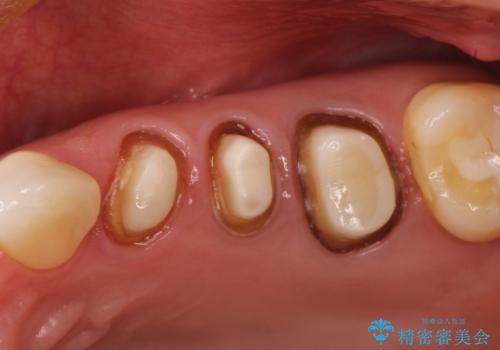

強度に優れたオールセラミッククラウンにて治療を行なっております。

3歯同時に治療を行うこと来院回数は4回で終了しています。